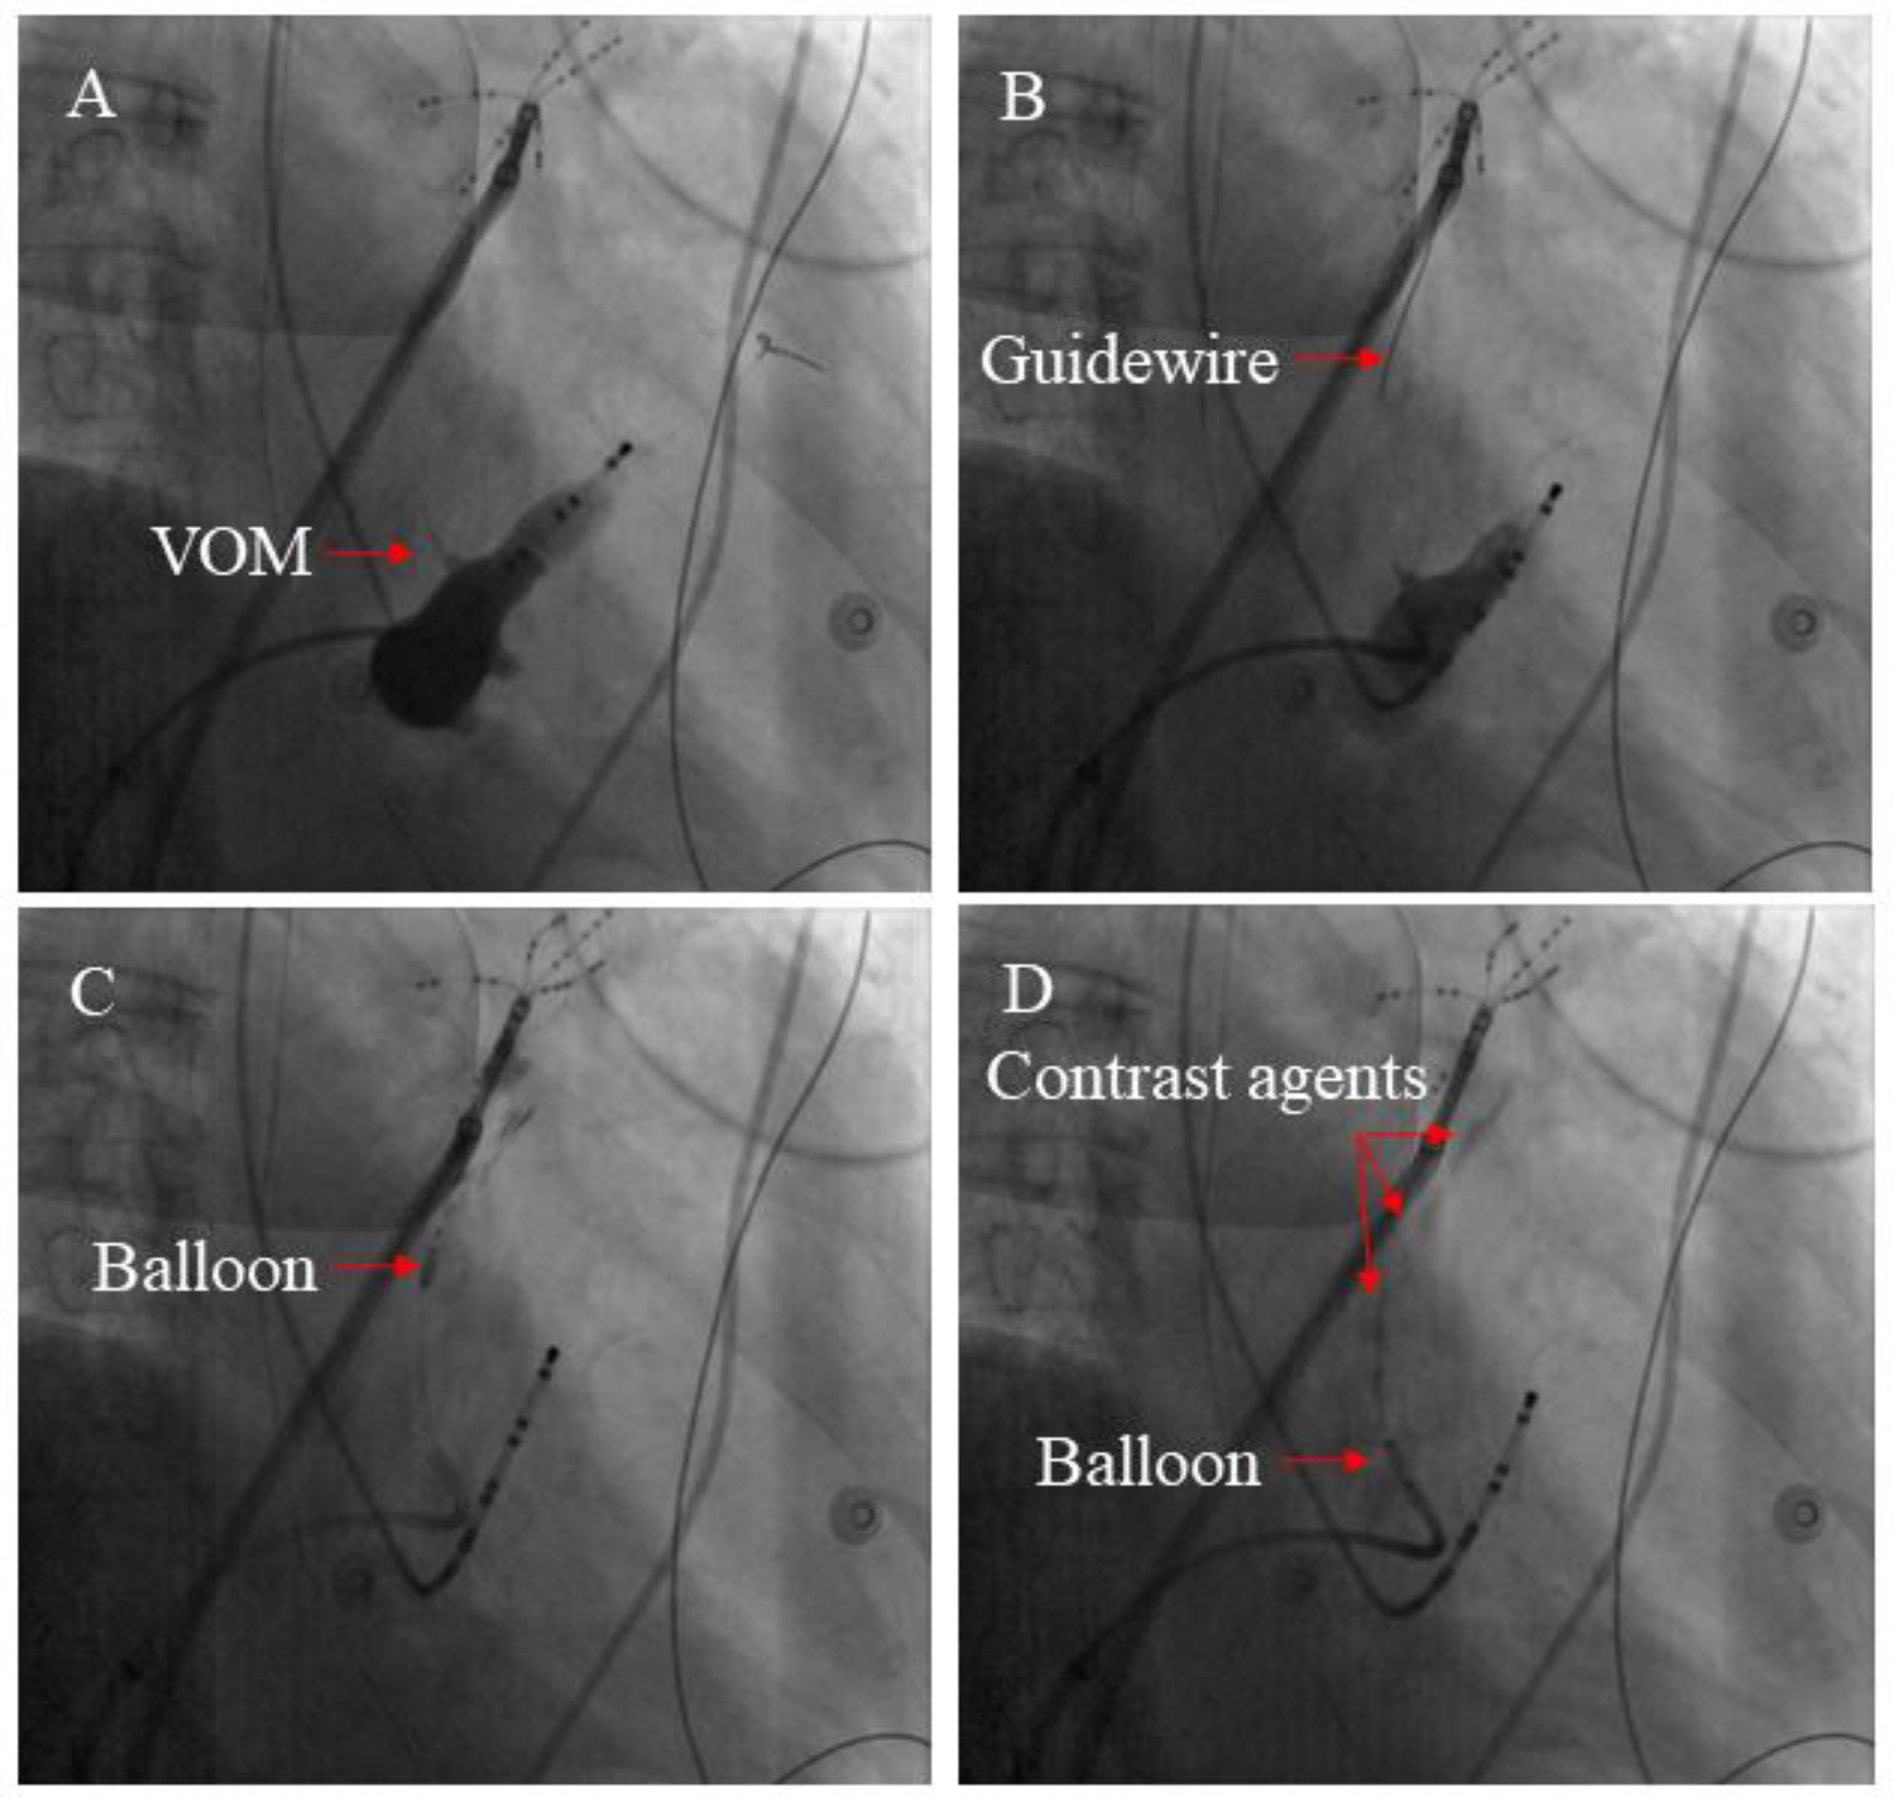

2.5 VOM-EI procedure

A previous study described the VOM-EI procedure in detail (14). A pre-molded Judkins Right 3.5 guide catheter (Cordis) was introduced into the CS under the guidance of a Runthrough NS guide wire (Terumo), and angiography was performed to visualize VOM. The Judkins Right 3.5 guide catheter was adjusted to make its tip enter or close to the proximal end of VOM, and the Runthrough NS guide wire was adjusted to make its tip located at the distal end of VOM. Under the guidance of Runthrough NS wire, the OTW balloon catheter (Boston Scientific) was placed into the distal VOM, dilated, and an iodine contrast agent was injected into it to confirm the blockage of the distal VOM blood flow. Slowly inject about 3–6 ml of absolute alcohol through the OTW balloon catheter, then withdraw the OTW balloon catheter to the proximal segment of VOM, and slowly inject about 3–6 ml of absolute alcohol according to the previous steps. Myocardial staining around VOM can be observed by performing angiography (Figure 1).

Figure 1

The main steps involved in the VOM-EI process. (A) An angiography of the CS vein demonstrated the presence of the VOM (see red arrow). (B) By inserting a guidewire (shown by the red arrow), the distal section of the VOM could be accessed. (C) Anhydrous ethanol was injected through the balloon catheter inflated at the distal segment of the VOM (red arrow indicating inflated balloon catheter). (D) The ablated myocardium can be colored with contrast agents by multiple injections of anhydrous ethanol (The red arrow indicates the contrast agents).